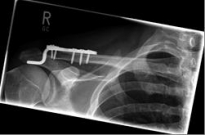

Schlüsselbein 4        Schlüsselbein 5

Pictures: Here, an angle-stable plate was used to supply the clavicle fracture near the shoulder joint. This plate makes it possible to anchor many screws in the fragment and thus obtain a good stabilization.